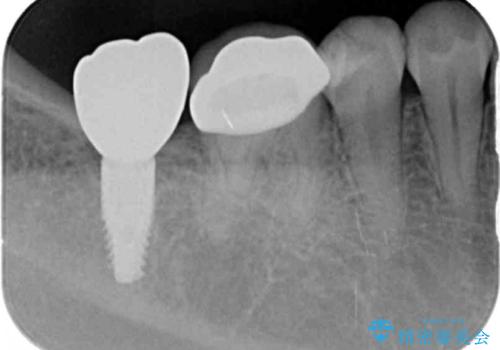

- 以前治療した歯がどんどん虫歯になり、いよいよ噛めなくなりこれで治療を最後にしたいと希望され来院されました。

全体的に多くの虫歯の発生が認められ、残せないところはブリッジ・インプラントを用い徹底的に虫歯を除去することで再発を防ぎ安定して噛める状態へとできるよう治療を計画します。